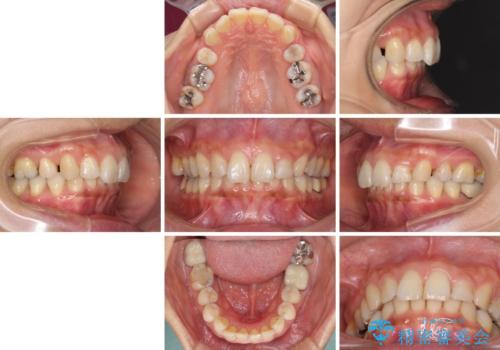

- 以前行った抜歯矯正が後戻りし、開いてしまったスペースが気になるとのことで来院された患者様です。

インビザラインを用いて開いてしまったスペースと前歯のデコボコを改善することとしました。

矯正治療後には気になっていた銀歯をセラミッククラウンやセラミックインレーにて治療することとしました。

上顎前歯を左右対称となるように歯列を整えたいとのことでしたが、すり減って形態が大きく異なっていたため、できる範囲での仕上がりとなりました。